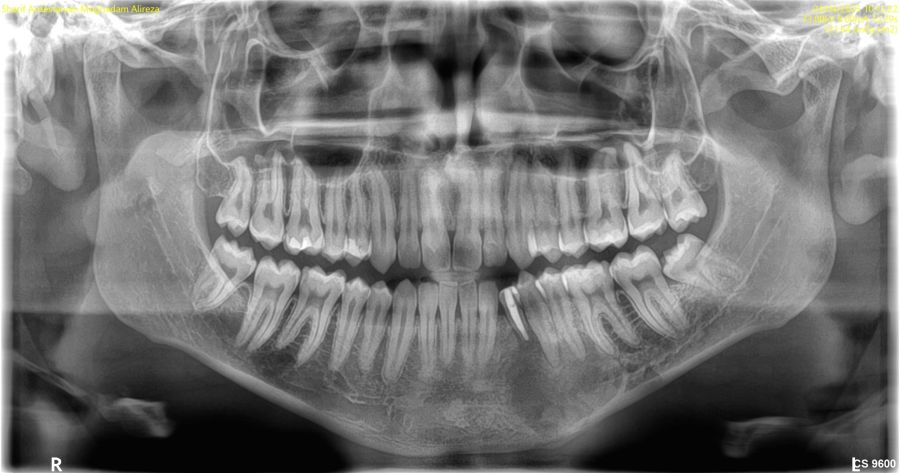

Tras estos hallazgos se solicitóun estudio mediante CBCT mandibular completo, que reveló los siguientes hallazgos en los cortes panorámicos: lesión radiotransparente delimitada y con un halo esclerótico casi completo, que se extiende en sentido mesiodistal desde la zona distal del canino temporal hasta el ápice del primer molar alcanzando la basal mandibular incluyendo la presencia de un canino mandibular (Figura 2).

Los cortes ortorradiales ofrecieron información sobre la ausencia de expansión de corticales, conservación de la cortical lingual y a la altura del segundo premolar ligera perforación de la cortical vestibular (Figuras 3A y 3B). Las reconstrucciones 3D corroboraron los hallazgos anteriormente descritos (Figuras 4A y 4B).

Su apariencia de lesión radiotransparenteunilocular, con contornos bien definidos y asociada a la corona de un diente retenido, son fácilmente detectables en la radiografía panorámica, si bien la CBCT, ofrecerá una mayor precisión en sus características y ayudará en el diagnóstico de presunción y en la orientación terapéutica11.